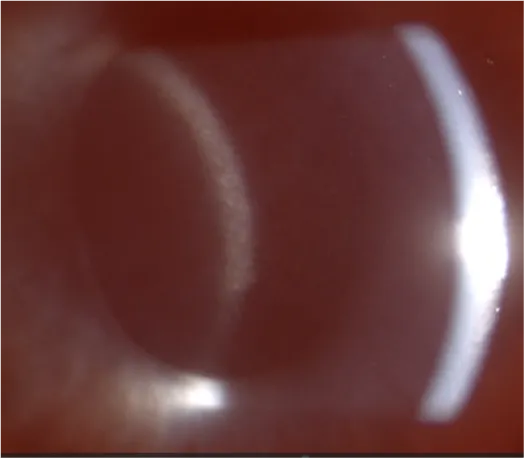

Tumor necrosis factor-alpha (TNF-α) is a key proinflammatory cytokine involved in inflammation. When administered intravitreally, TNF-α induces rapid infiltration of inflammatory cells in the anterior uvea and aqueous humor, mimicking features of acute uveitis. First demonstrated in rabbits by Rosenbaum et al. (1988) and further characterized by Fleisher et al. (1990), this model has since been widely used and validated as a reliable platform for studying ocular inflammation and testing anti-inflammatory therapies.

Clinical evaluation of uveitis severity is performed by an experienced veterinarian using slit-lamp biomicroscopy and scored according to the Modified Hackett-McDonald and the SPOTS (Semiquantitative Preclinical Ocular Toxicology Scoring) grading system.

Inflammation peaks on Day 7 and resolves by Day 14.